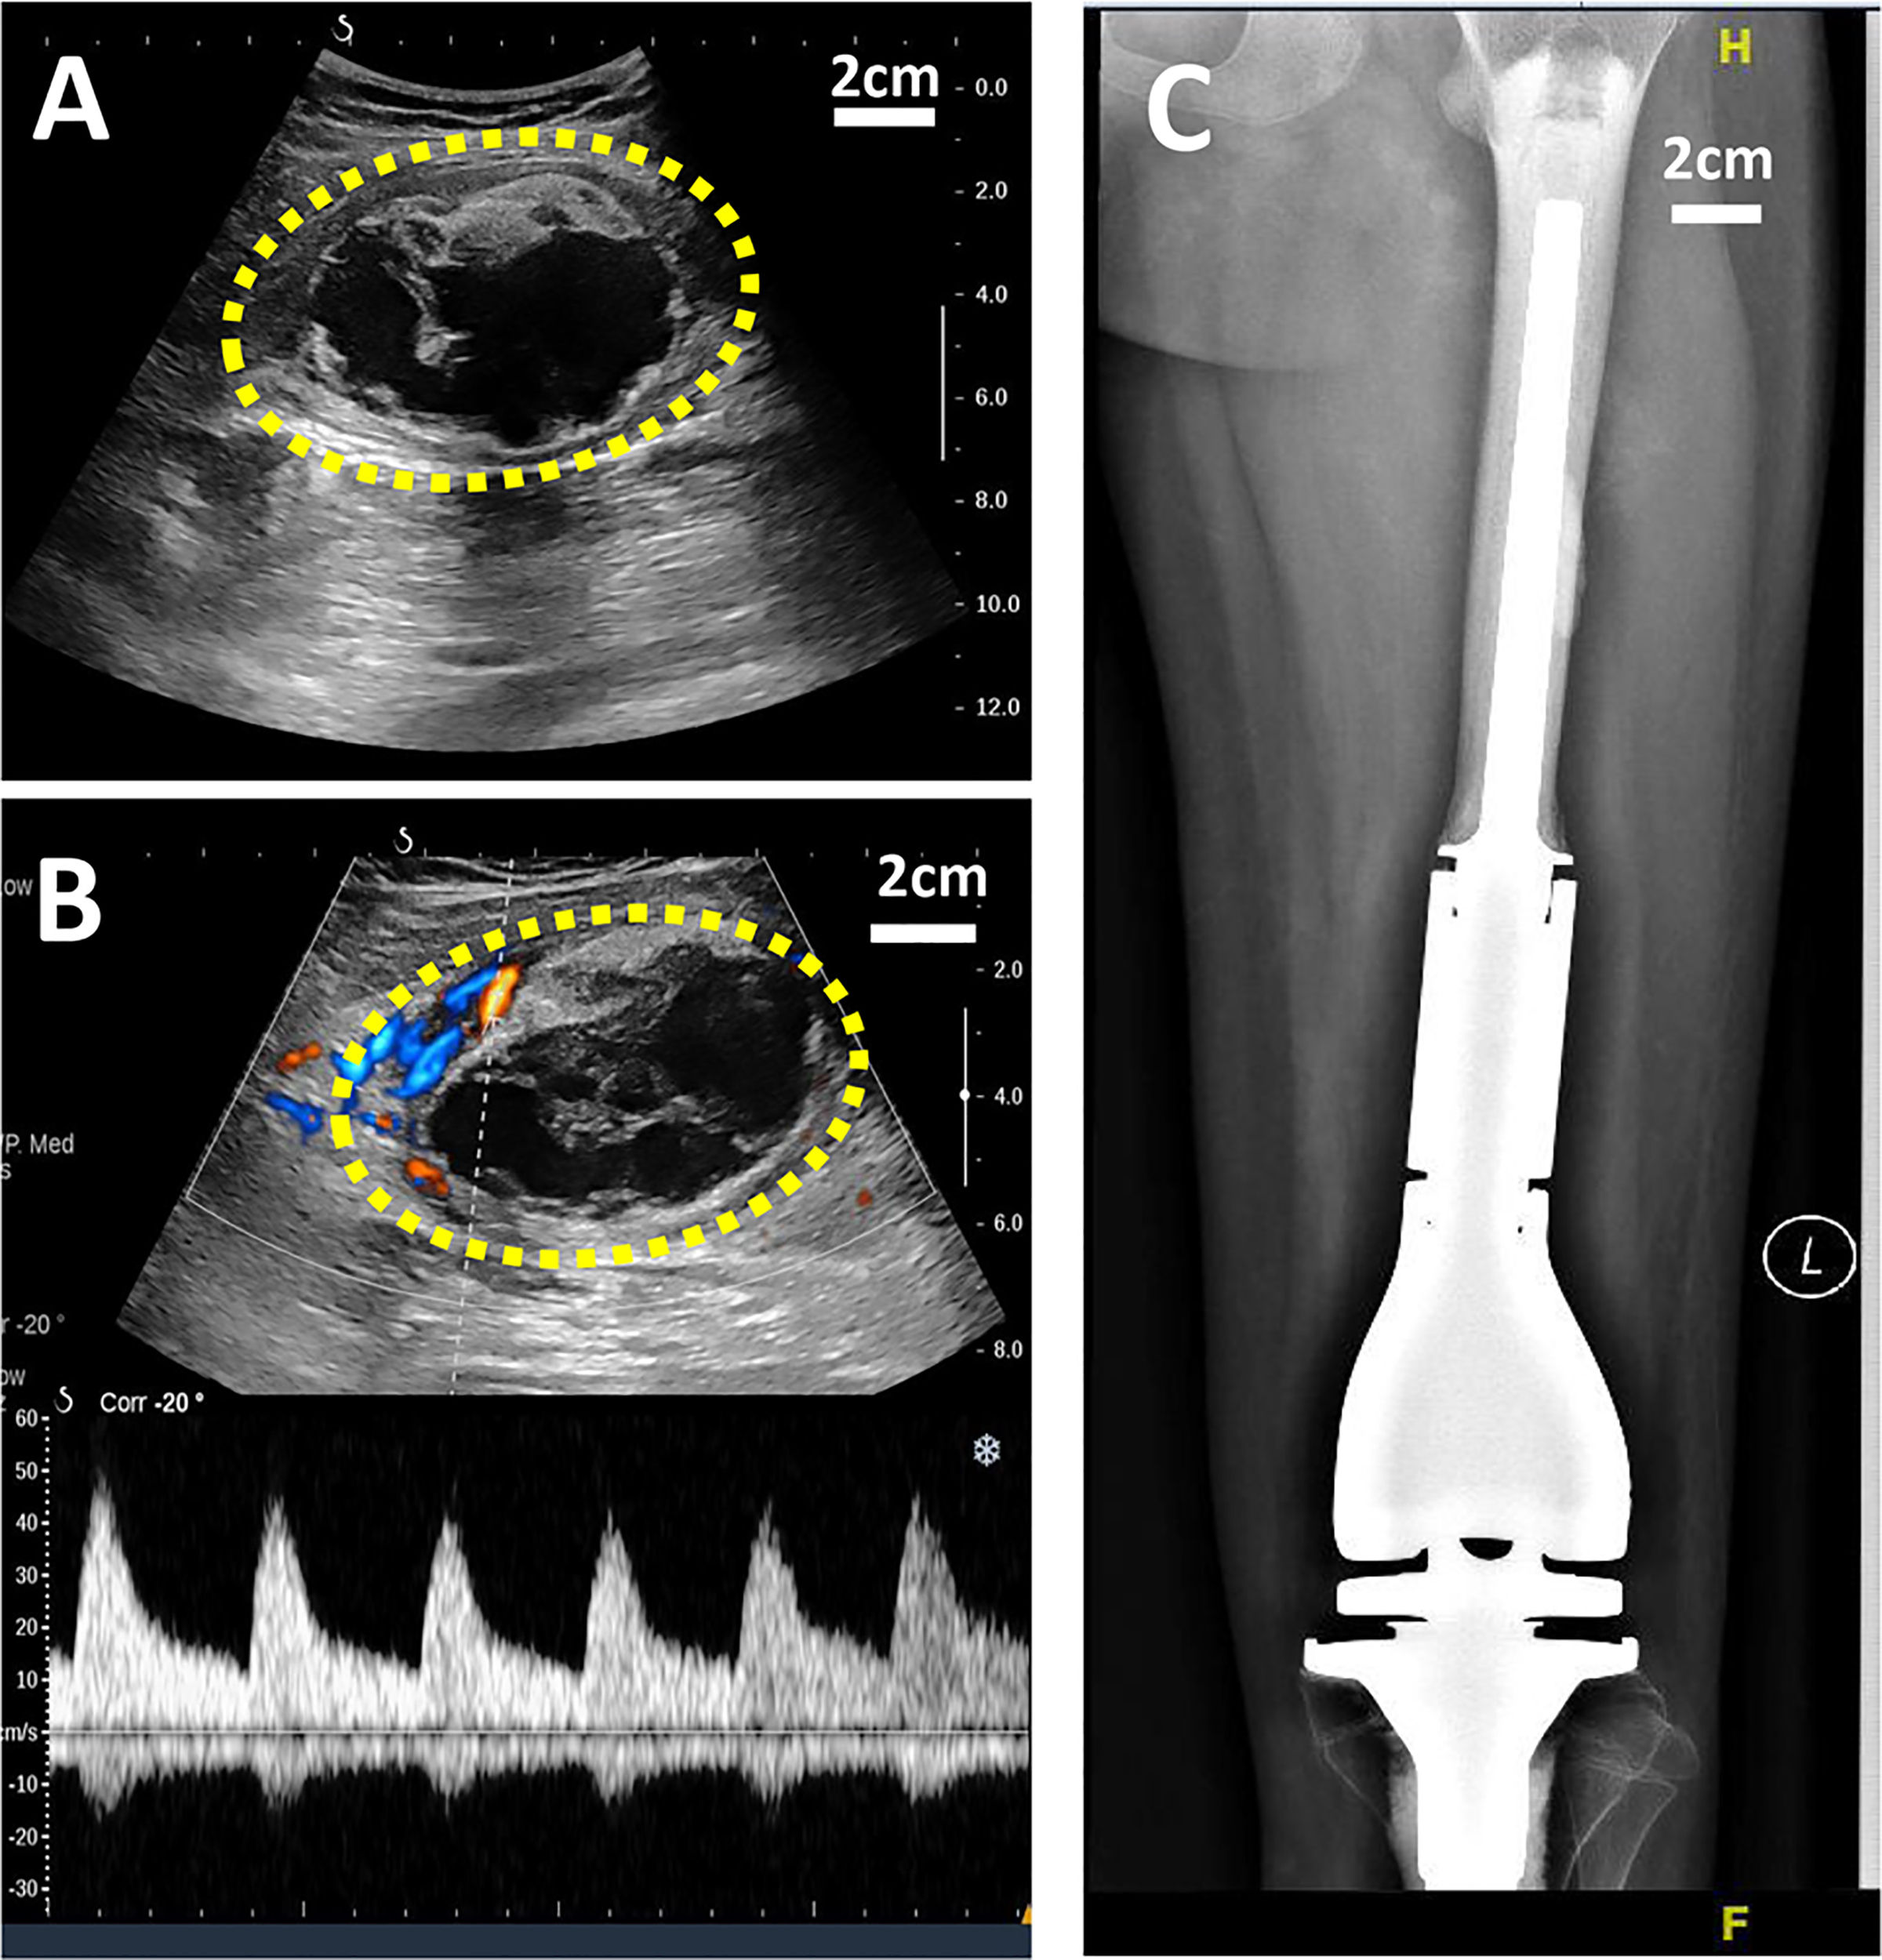

X-ray is a routine means of postoperative monitoring, which has advantages in showing abnormal changes in bone. Identifying a well-defined border is crucial for differentiating heterotopic ossification from local recurrence (20). However, it often misses minor lesions, bone marrow disease, and joint and soft tissue disease. As shown in Figure 2, it was easy to see the lesion in US but not in an x-ray image. CT has a higher spatial resolution than x-ray and can provide more information about soft tissue lesions. However, whether the benefits of using CT for early detection of lesions outweigh the risks of radiation exposure and false positives remains to be further investigated. For the cases with artificial prosthesis replacement or metal internal fixation implantation, significant artifacts are generated on CT, which affect the observation of local tissues (21, 22). As shown in Figure 3, it was easy to see the lesion in US but not in CT due to the imaging artifacts of metallic prosthesis. Systemic bone scanning with 99mTc-MDP can reveal local recurrence, systemic bone metastasis, and skipping lesions. However, the high uptake area cannot distinguish between tissue repairing response, residual disease, or recurrent lesions. A local recurrence may be found at the primary site, the stump, the resection site, or near the prosthesis. When the recurrent tumor is localized in soft tissue and does not contain sufficient mineralized osteoid, it may not be detected by conventional radiographs or even bone scans (23).

Figure 2 US and X-ray images of a 11-year-old girl with OS local recurrence after limb salvage with metal implants. It was easy to see the lesion in US but not in X-ray image. (A) A heterogeneous echogenic mass in the longitudinal plan of US image. (B) Color Doppler and power Doppler US image of the mass. (C) No obvious lesion was found I the X-ray image.